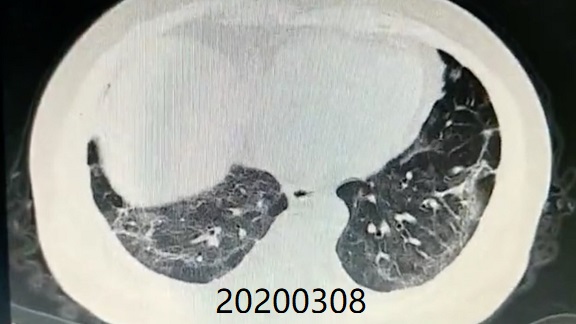

Comparison of CT imaging of chest before and after treatment with the patient (Mr. Zhang)